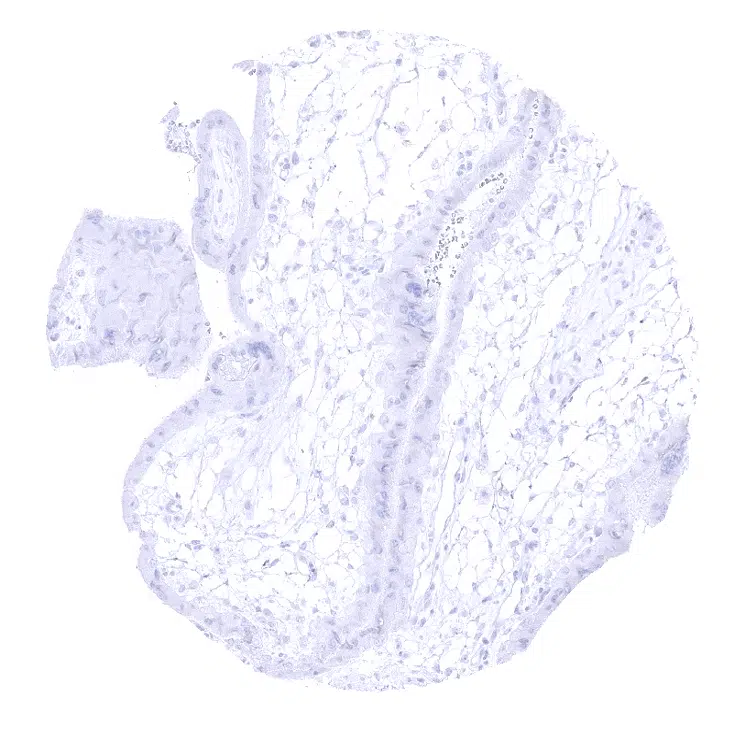

Endocervix – A weak to moderate MUC6 immunostaining may be seen in individual endocervical glands.

Endocervix – MUC6 immunostaining ranges from weak to moderate in endocervical glands.